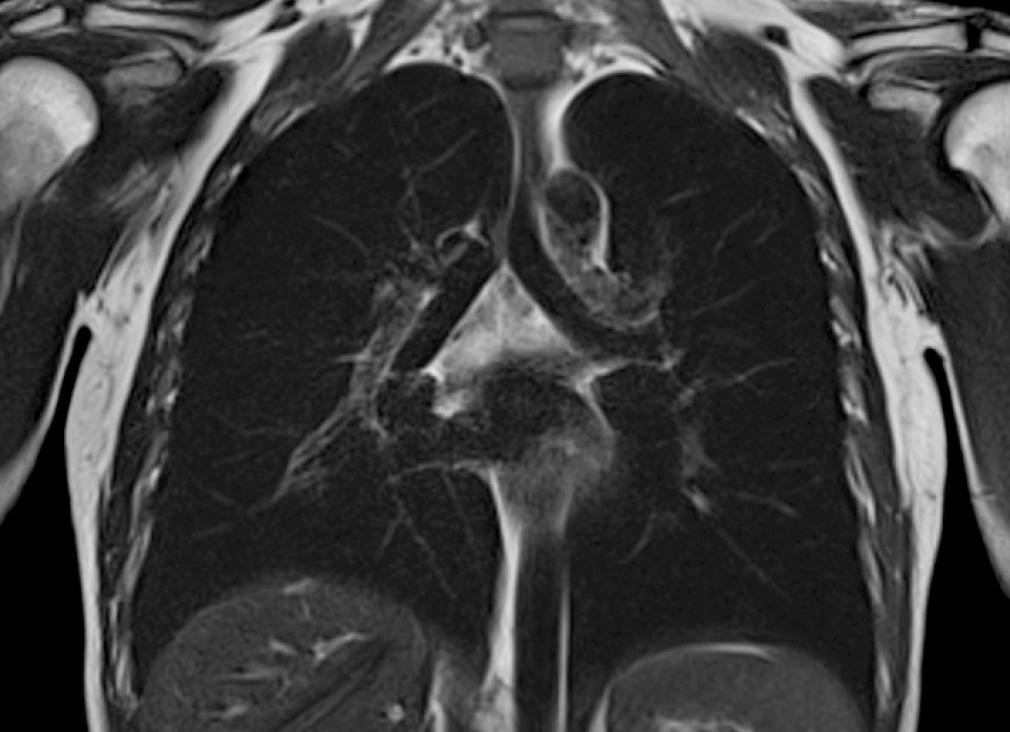

МРТ снимок больного раком легкого

МРТ легких и бронхов становится альтернативным методом диагностики заболеваний дыхательной системы. Изучение строения легких с помощью МРТ основано на получении ответного сигнала от протонов тканей и жидкостей человеческого тела, так называемом, явлении ядерно-магнитного резонанса.

• Опухоли (в области средостения и при распространении на грудную клетку)

• Дифференциальная диагностика ателектаза и опухоли

• Дифференциальная диагностика опухолей средостения

Мрт легких – качественный метод оценки состояния легочной ткани, средостения и мягких тканей на основе регистрации радиоволн, полученных при колебании атомов водорода под влиянием магнитного поля.

Мрт грудной клетки показывает структурные изменения клеток, состоящих из воды. Радиосигнал, полученный от легочной паренхимы при воздействии магнитного поля достаточно информативный для определения патологических образований, расположенных на границе раздела сред: между воздушными альвеолами и паренхиматозными клетками.